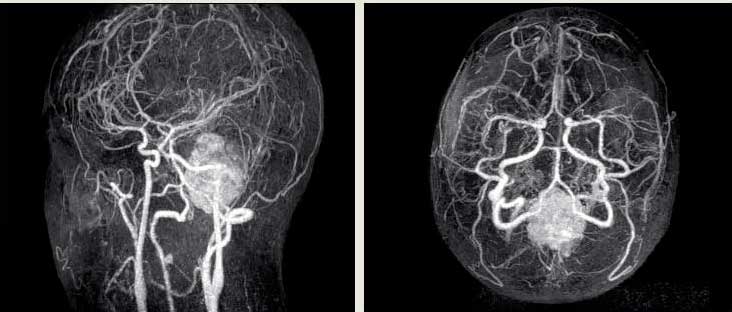

- Ангиография дает наиболее полную картину состояния сосудов без введения в них контрастных веществ. С ее помощью получают объемное изображение поврежденной артерии, что позволяет судить о разновидности, размерах и форме выпячивания.